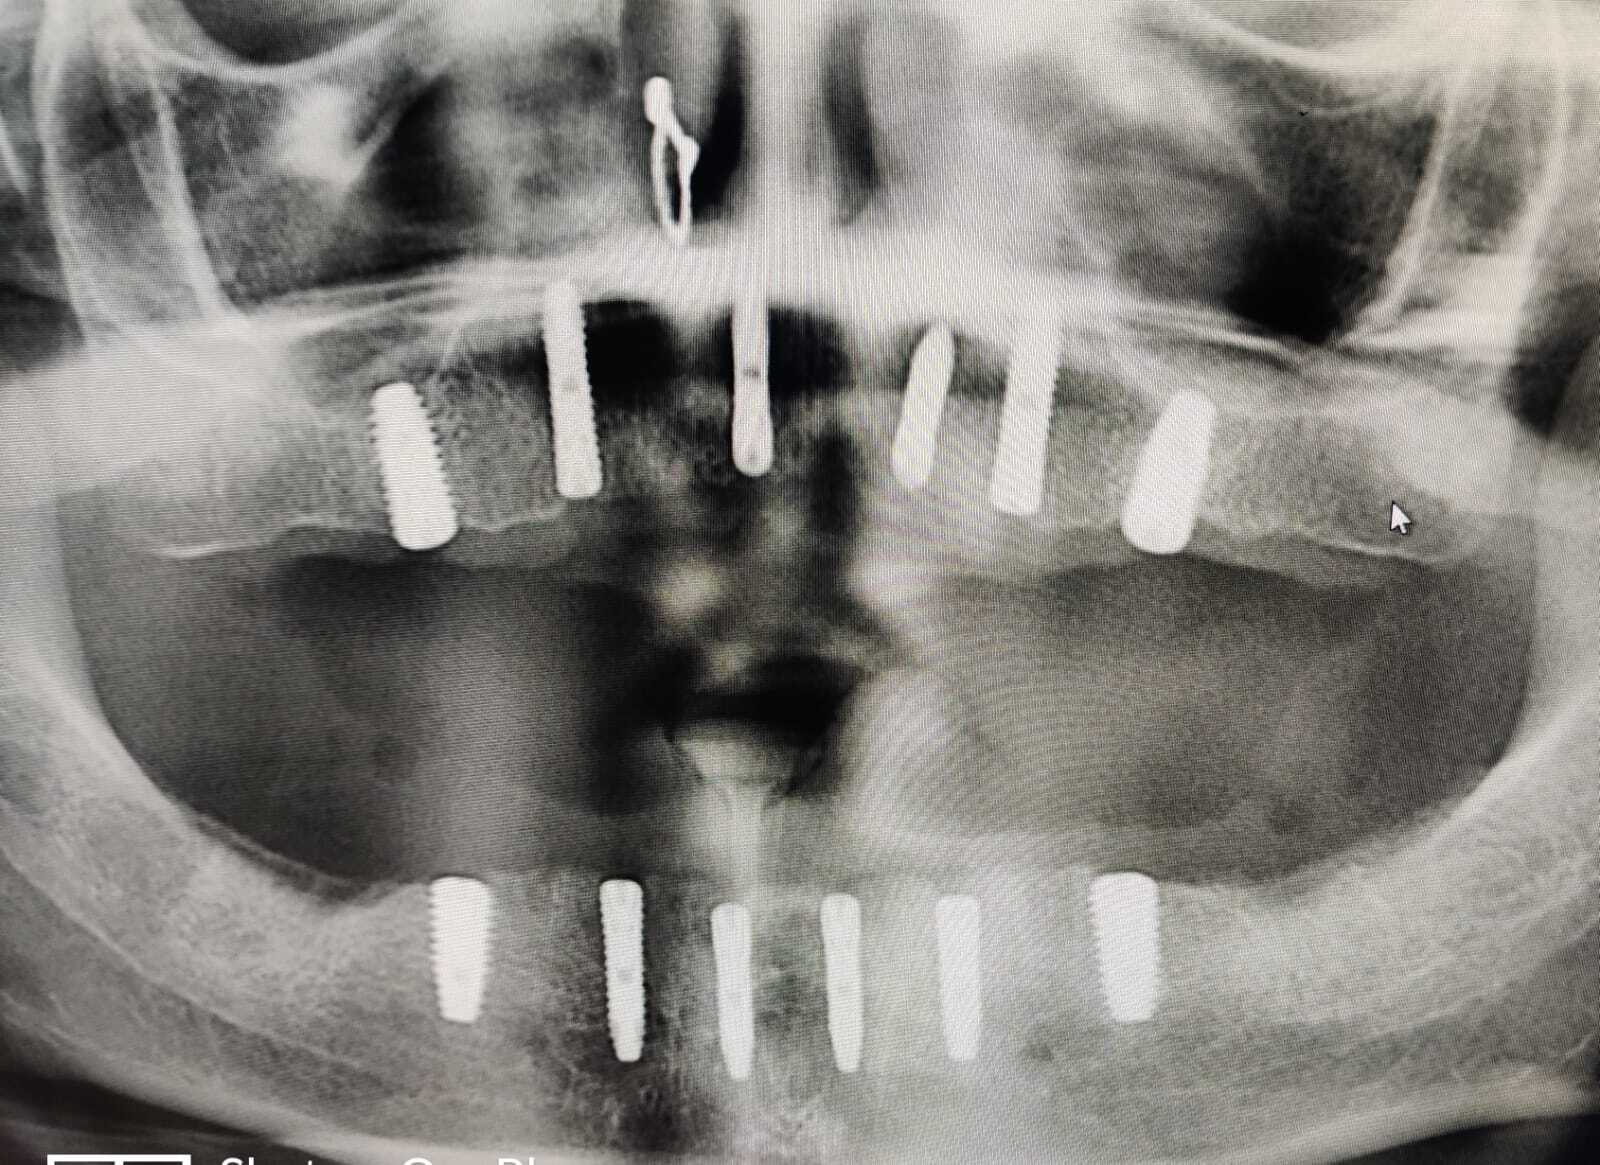

Dental Implants

A dental implant is a root of an artificial tooth. It is fixed into the jawbone and so it can facilitate permanent artificial teeth. Dental implants can support a single artificial tooth or multiple artificial teeth. They are made of dental material like titanium or zirconium. Unlike dentures or other dental restorations like dental bridges, artificial teeth fixed on top of dental implants are closest to natural teeth. They provide superior functionality enabling chewing of food and clear speech. Dental implants are fixed into the jawbone with a dental surgery. Once dental implants are firmly fixed, artificial teeth, dentures, or crowns are placed.

Sinus Lift Surgery

In order to successfully place dental implants you need sufficient bone. In certain situations dentist need to perform specific procedures in order to create bone volume. One such procedure is sinus lift. The maxillary sinuses are empty rooms that have nothing at all in them. When upper teeth are removed, there is often just a thin wall of bone separating the maxillary sinus and the mouth. Dental implants need bone to hold them in place so when the sinus wall is very thin, it is impossible to place dental implants in this bone. There is a solution called a sinus graft or sinus lift graft. The dental implant surgeon enters the sinus and sinus membrane is then lifted upward and donor bone is inserted into the floor of the sinus. After several months of healing, the bone becomes part of the patient’s jaw and dental implants can be inserted and stabilised in this new sinus bone. The sinus graft makes it possible for many patients to have dental implants when years ago there was no other option other than wearing loose denture.